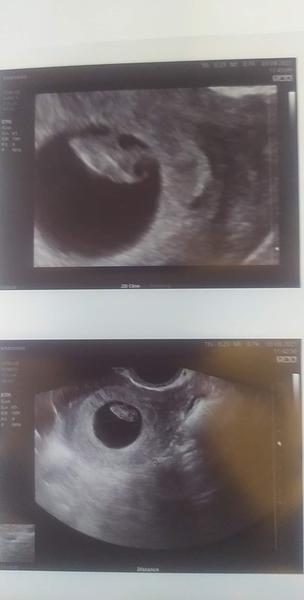

Děvčátka nekdo už 8 den ducha na testu po Ket 5 denního embrya? Nebo je to brzo?